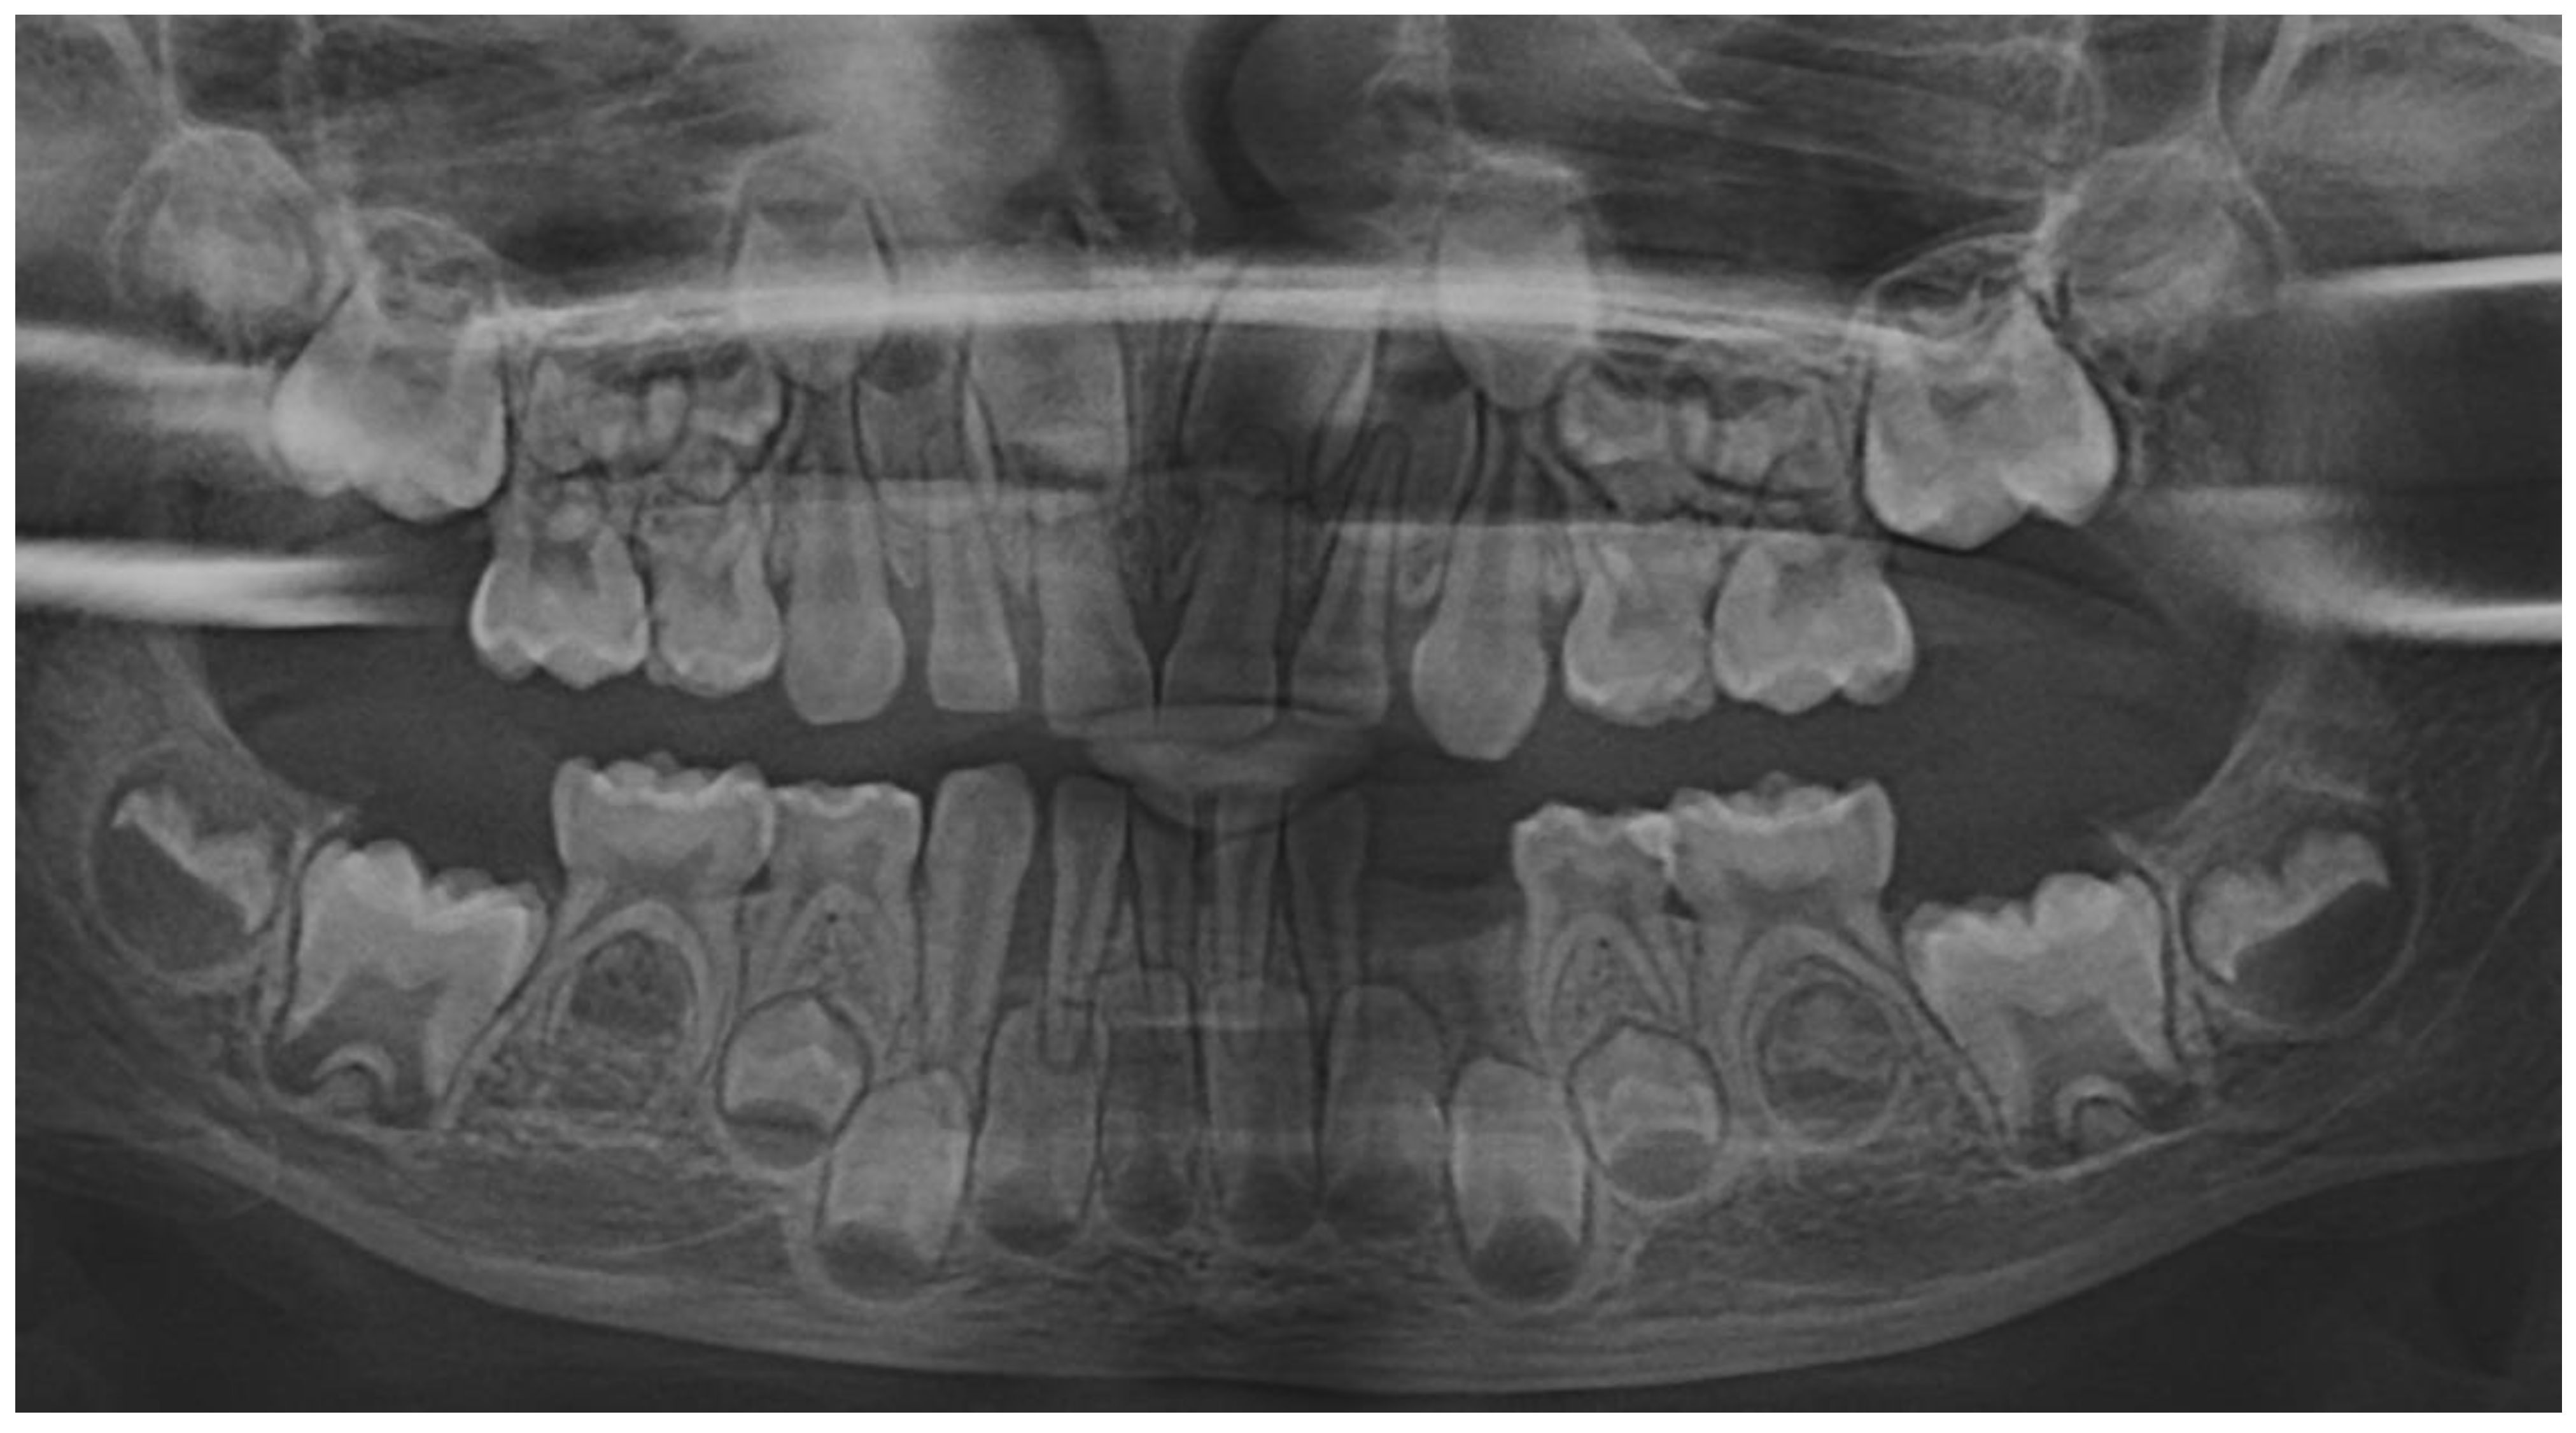

In August 2023, the family consulted another clinician abroad (2nd of August, Klausenburg/Cluj-Napoca - Romania) since parent’s concerns related to deteriorating the local conditions (inflamed periodontium around lower temporary canine and enhanced movement, Figure 2). The parents presented the entire documentation gathered from previous examinations including paraclinical tests results and x-rays [1]. After reviewing familial history and clinical and paraclinical examinations (3rd of August) the initial hypophosphatasia/hyperphosphatasia suspicions were dismissed (also confirmed by late September 2023 genetic test negative results) and the Stage IV grade C localized periodontitis/pre-puberal localized aggressive periodontitis-LPP was made. No orthodontic problems were detected during the clinical examination (also confirmed by previous clinical exams), and only the hyper-eruption of the temporary left canine due to advanced periodontal loss and surrounding inflammation (Figure 2) [1]. When setting up the LPP diagnosis, the previous x-rays (Figure 1) were taken into consideration along with girls other paraclinical results. For laboratory confirmation, a periodontopathic bacteria sample was taken (3rd of August). Since the advanced localized periodontal loss and tooth movement only professional hygiene and adjuvant topical applications with amoxicillin and metronidazole association around the inflamed periodontal pocket for a period of 10 days was prescribed. The parents were informed about all these above-mentioned issues, and the most-likely loss of the tooth but also the necessity of instituting a general antibiotic treatment and follow-up of the case. The family left Klausenburg (Romania) 5th of August. The periodontopathic bacteria test came highly positive on the 16th of August 2023 with Fusobacterium nucleatum/periodonticum and Capnocytophaga. The tooth was finally lost in early September (Figure 2) [1].

The unusualness of this case is due to several aspects. The first is related to the extremely young age of the patient (i.e., 4 years-old in February 2023, temporary dentition), with an insidious onset, and apparently no familial aggregation or history. The second aspect is related to the misdiagnose to metabolic diseases (i.e., hypophosphatasia/hyperphosphatasia) despite the initial radiographical (i.e., Figure 1) and clinical examination that suggested a clear picture of an unusual LPP (e.g., the lower left canine involvement). The third aspect is related to the lack of therapeutic measures that rapidly set the course for the periodontal and 7.3 loss, in an interval of around 7 months (Figure 2) and the further progression involving other oral sites (Figure 3 and Figure 4). The fourth aspect is related to the evolution under adequate treatment (despite no written report to guide it) and the periodontal gain over a period of around 8 months following the antibiotic therapy (Figure 5 and Figure 6).

Figure 2. Images of the lower left canine: A and B – advanced mobility and hyper-eruption due to advanced periodontal loss and inflammation (2nd of August 2023), C – 7.3, lost in September 2023.